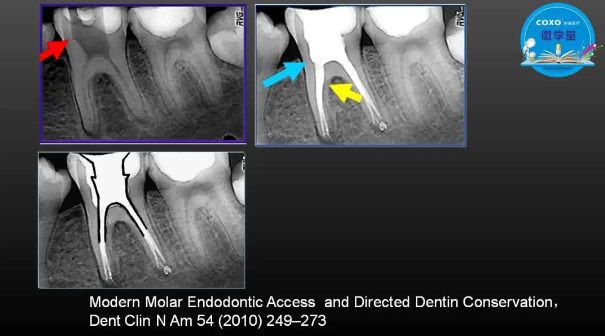

主任醫(yī)師,牙體牙髓副主任, 廣東省口腔醫(yī)院牙體牙髓科 主任醫(yī)師。2003年碩士研究生畢業(yè),研究方向為牙體牙髓病學,擅長于牙體牙髓病的診斷、齲齒、牙髓炎、根尖周病的治療以及前牙美容修復。